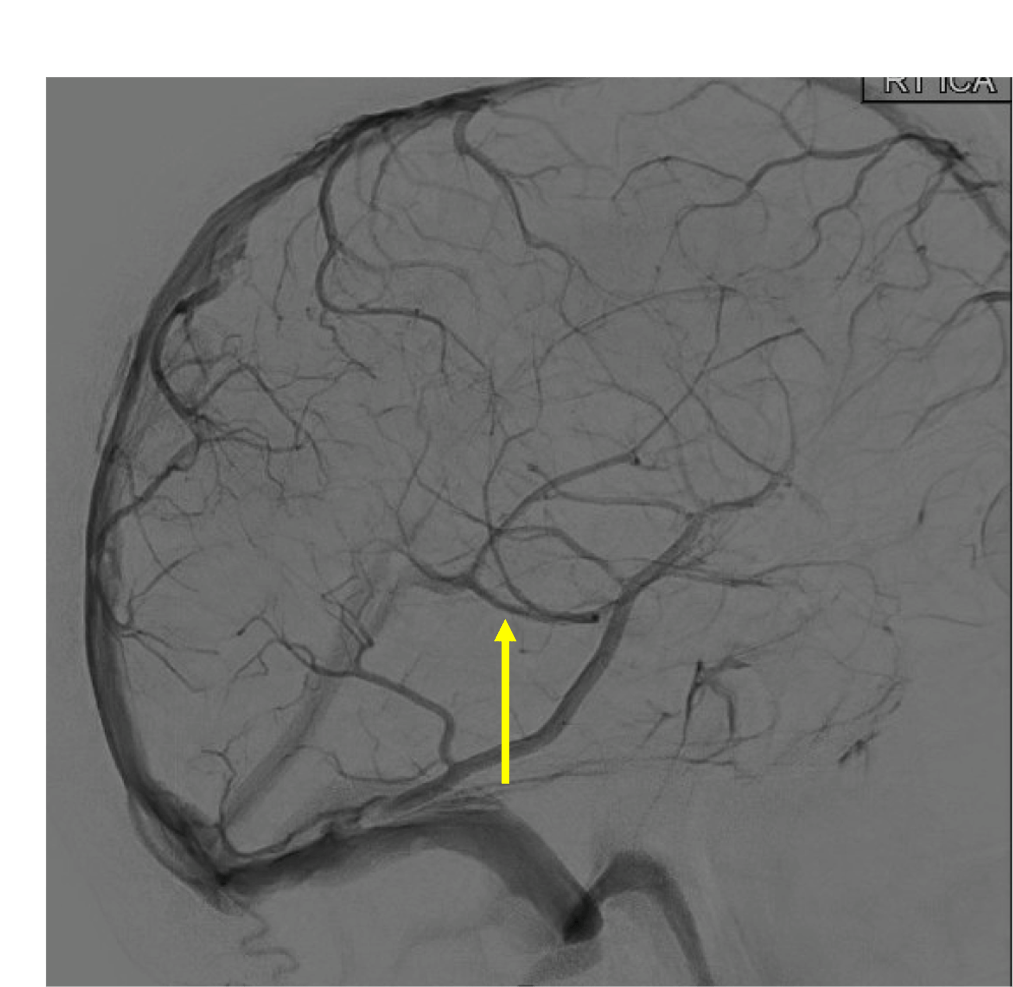

Which vessel is the arrow pointing toward?

Anterior choroidal artery